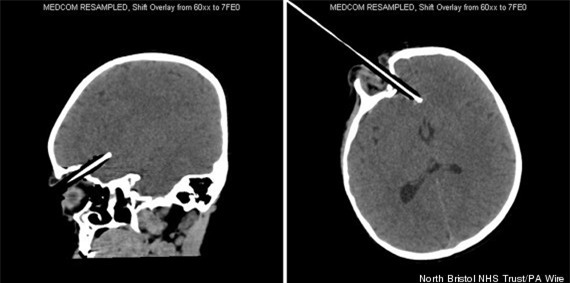

Hình

ảnh chụp cho thấy cây bút đã sượt qua nhãn cầu và những chỗ chí tử

trong não của bệnh nhân một cách thần kỳ. Chỉ cần đường đâm chệch một

chút thôi sẽ gây tổn thương đến mạch máu lớn trong não và Wren có thể đã

không giữ được tính mạng. Các bác sĩ sau đó đã tiến hành mở hộp sọ để

lấy cây bút ra bởi cú đâm quá mạnh khiến cây bút lún sâu đến gần 4cm vào

trong não của cô bé.